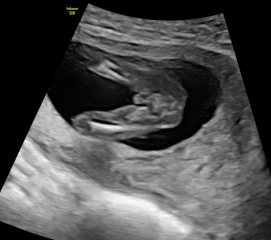

Had a private gender scan at 15+5 weeks and was told it was a girl but i’m unsure after looking at the scan images.

Private Gender Scan Right?

It's so hard to tell from these images, it becomes more accurate as your pregnancy progresses so maybe wait for the NHS one..